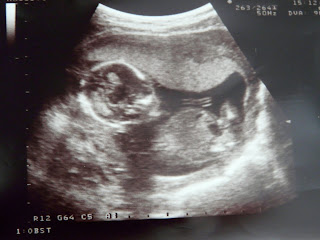

Om 11u hadden we vandaag een afspraak voor een nieuwe echo. Ze zouden nu ook aan de hand en mijn bloeduitslag een berekening doen hoeveel kans we hadden op een kindje met syndroom van Down.

Hoe grappig. Onze scampi lag mooi en ze kon alles heel goed opmeten. Scampi zat eigenlijk constant naar ons ze zwaaien. Zo lief :-)

Ze heeft zelf een 3D foto gemaakt omdat we zo lang hadden moeten wachten.

(13 weken zwanger 6,5 cm)

De berekening was heel goed. 1 kans op 23 000 of zoiets :-)